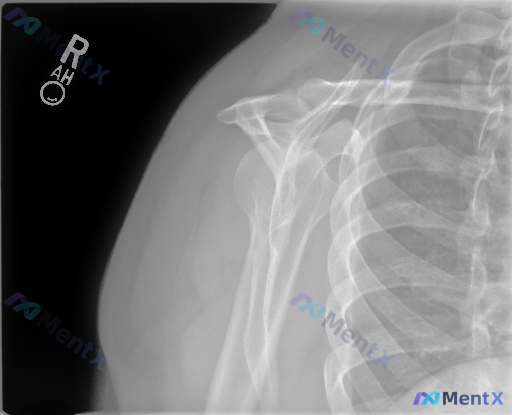

一份右侧肩部正位X光,影像科的结论写得很明确:

- 骨性结构完整,未见骨折、脱位、骨质破坏

- 各关节对位、间隙正常

- 肩峰下/大结节上方未见明确钙化影

- 无明显骨赘、囊性变或骨质疏松

- 软组织也没看到明显肿胀

但问题是——这份资料在开头被标记了「存在异常」。